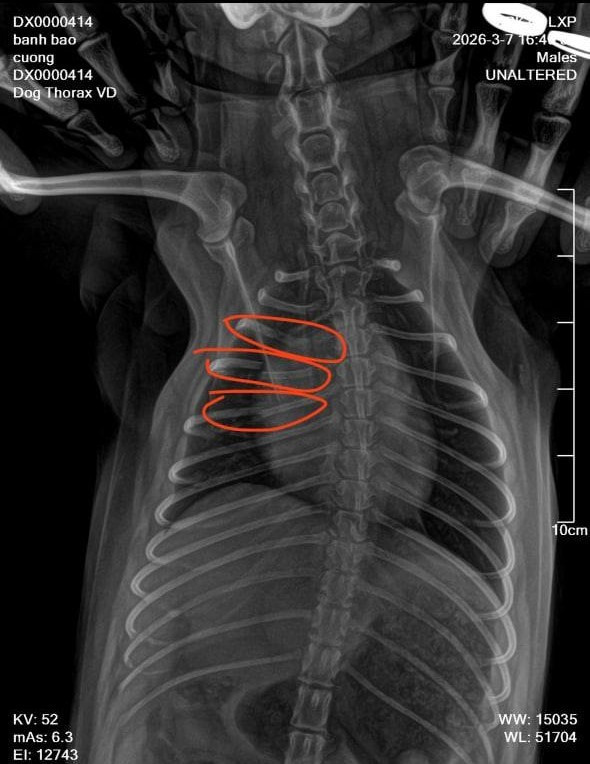

"Lúc đó trong tiệm không có ai cả, vợ tôi cũng ra ngoài. Tầm 15 phút sau vợ tôi trở về thì thấy chú chó kêu gào đau đớn nên đưa tới phòng khám thú y. Kết quả chụp phim cho thấy chú chó bị gãy tới 3 xương sườn. Vì chó cưng của tôi nhỏ quá nên bác sĩ bảo không thể bó bột được, chỉ đợi tự liền xương và phục hồi", anh xót xa.